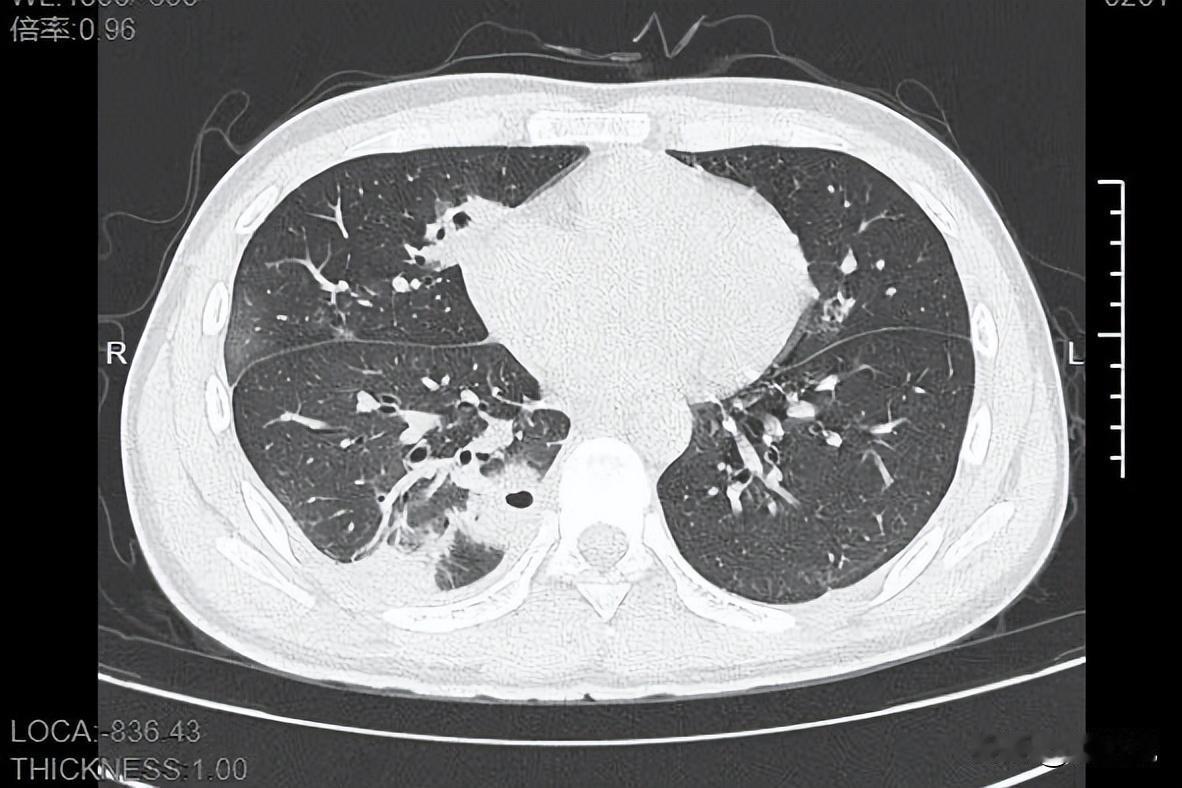

又犯了,哮喘。 大半夜的,就这么直挺挺地坐着,不敢躺下。 一躺下,感觉整个肺就像被人攥住,拼了命地吸,进来的气却只有一丁点儿。 那是一种什么感觉呢? 就是你明明在海里,却快要渴死了。空气到处都是,但没有一丝是属于你的。 吊瓶已经打了五天了。 胳膊上全是针眼,青一块紫一块的。 克林霉素,阿奇霉素,氨溴索……这些药名,我他妈背得比我老板的名字还熟。 结果呢?屁用没有。 今天赌气停了一天,以为能缓过来。 结果现在,报应来了。身体比谁都诚实。 喘。 一声接一声,像个破风箱。 自己都嫌自己吵。 往年,三四天就压下去了。生龙活虎的。 今年这是怎么了? 是病毒变强了,还是我变弱了? 明天还得去医院,伸出另一条胳膊,继续当那个“药瓶子”。 医生,求你了,给换个猛药吧。 或者,谁能告诉我,到底怎么才能像个正常人一样,好好地…… 睡一觉。 就这么简单。